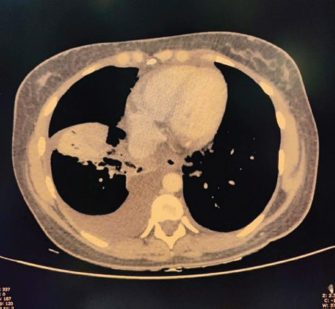

USG’s whole abdomen revealed hepatomegaly and mild to moderate ascites. In view of melena and thrombocytopenia, 6 units of random donor platelets were transfused. A workup for fever with thrombocytopenia and polyserositis was started. Dengue RTPCR, NS1 antigen, IgM, Weil felix, and VDRL were negative. Viral markers (HIV/HBsAg/Anti HCV/Anti HAV IgM/Anti HEV IgM) were negative. Scrub IgM, Brucella IgM, Urinary legionella antigen, CMV PCR, and Leptospira IgM were negative. Malaria Ag and P/S for the malaria parasite were negative. The widal test and Typhidot IgM were negative. CPK and CK-MB were negative. Stool occult blood (three samples) were negative. Covid PCR was negative. Blood and urine C/S were negative. Urine KOH revealed few budding yeast cells. Urine fungal culture was negative. Workup for EBV revealed 24,300 copies of EBV RTPCR and EBV IgM and IgG were positive. We did an autoimmune workup considering a young female with polyserositis but both ANA by Immunofluorescence and ANA profile were negative. Direct and indirect Coombs tests were negative. By the end of first week of admission, thrombocytopenia started improving but she had a persistent cough and fever although spikes were reduced. A 2D echo revealed trace pericardial effusion. Repeat Chest X-ray revealed persistent bilateral pleural effusion (Right > Left) (Fig. 2). In view of persistent effusion, we decided to perform a CECT chest and abdomen which revealed evidence of moderate right pleural effusion, minimal fluid in the left pleural cavity with atelectatic changes in the adjacent lung, oedematous thickened gallbladder and mild ascites (Figs. 3 and 4).

Fig. 3. CECT chest suggestive of bilateral pleural effusion Right > left, minimal pericardial effusion.